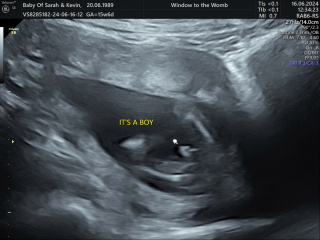

Lunamoon23 · 14/06/2024 18:49

Had my first scan today! Everything looks perfect thank god! I'm further along than expected at 13 weeks + 4! Was a very active little bean! Thought I'd share my scan photos to see if anyone has any nub theorys??

Boy / Girl?

littlepanda88 · 14/06/2024 19:08

@Lunamoon23 aww what a lovely scan!! Going by the nub I'd say boy!! :-) during my scan baby was so wriggly, it was hard to get decent shots! :)

Hahaha EVERYONE so far has said boy, I think the same, my husband is one of 4. 3 boys, 1 girl.

@HopefulElle @RedRobyn2021 @littlepanda88 we did a test of the nub theory tech last night, and it came back with 90% probability of boy!! So it looks like everyone may well be correct!!

I've attached my nub theory results for fun!